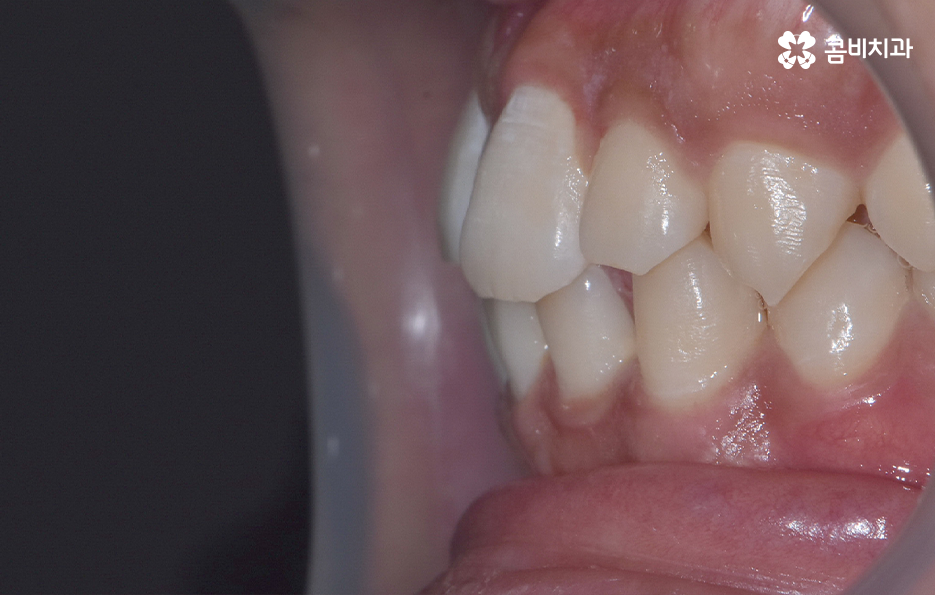

과잉치 중에서는 어떤 치아가 과잉치인지 구분이 어려울 정도로 일반적인 정상 치아의 크기와 비슷한 크기와 형태를 띄는 경우도 있는 반면에 위 사진의 케이스는 첫번째 앞니와 앞니 사이에 유독 작은 왜소치가 있는 형태이기 때문에 치아의 기능적인 문제 보다는 심미적인 개선을 필요했던 케이스로 볼 수 있어요

그나마 다행인 점은 앞니만교정을 하더라도 치아의 교합이나 골격적인 부분, 얼굴형 등에 있어서 큰 지장은 없던 경우였는데요. 물론 아랫니가 다소 벌어져 있기 때문에 전체교정을 하면 더 좋은 결과를 얻을 수 있었겠지만 환자분의 니즈에 있어서 앞니만교정을 빠르게 원했던 사례이기 때문에 앞니 부분의 과잉치 발치 후 앞니만교정을 부분적으로 진행했어요

과잉치로 인해서 치아 배열이 전체적으로 불규칙해지는 경우도 있고 돌출입의 형태로 나타는 경우도 있지만 다행이도 입술라인이나 얼굴형에 있어서 돌출은 크지 않은 상태였다는 점도 앞니만교정을 해도 어느정도 좋은 결과를 낼 수 있던 케이스로 볼 수 있어요

과잉치로 인해 말그대로 치아의 정상 범위 이상으로 치아가 배열되기 때문에 다른 치아의 배열에도 악영향을 주는 경우가 많지만 위 환자분의 케이스의 경우에는 치열 자체는 전체적으로 가지런한 편이라는 점과 특히 턱뼈가 넓은 편이라는 점에서 전체교정을 하지 않았어도 환자분이 원하는 치료의 목표는 달성할 수 있었어요

치아교정 기간은 각 환자분들에 따라 천차만별이기 때문에 정확하게는 각 환자분들의 상태를 직접 확인해봐야 하며 누구나 앞니만 부분적으로 교정이 가능한 것은 아니기 때문에 정밀검진이 우선적으로 필요하며 위 환자분의 경우에는 과잉치를 발치하고 교정기 장착 후에 약 6개월 정도가 지나서 교정기를 떼어낼 수 있었어요